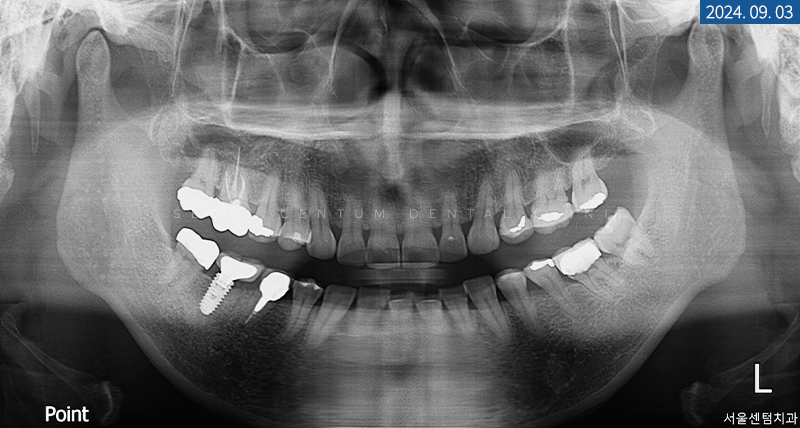

정확한 구내 파악을 위해

파노라마 엑스레이를 촬영해 보니

어금니 임플란트 식립과 크라운 수복,

신경 치료, 보철물로 때운 곳이 보였습니다.

다행히 라미네이트 받기를 원하시는 전치부에는

미세 크랙 외에 큰 이상 소견이 보이지 않아

도재를 아름답게 부착해 드리기로 했는데요.